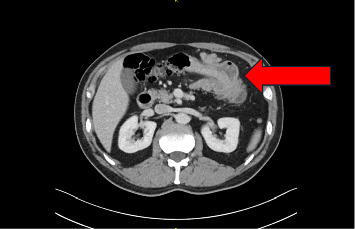

Abstract Image